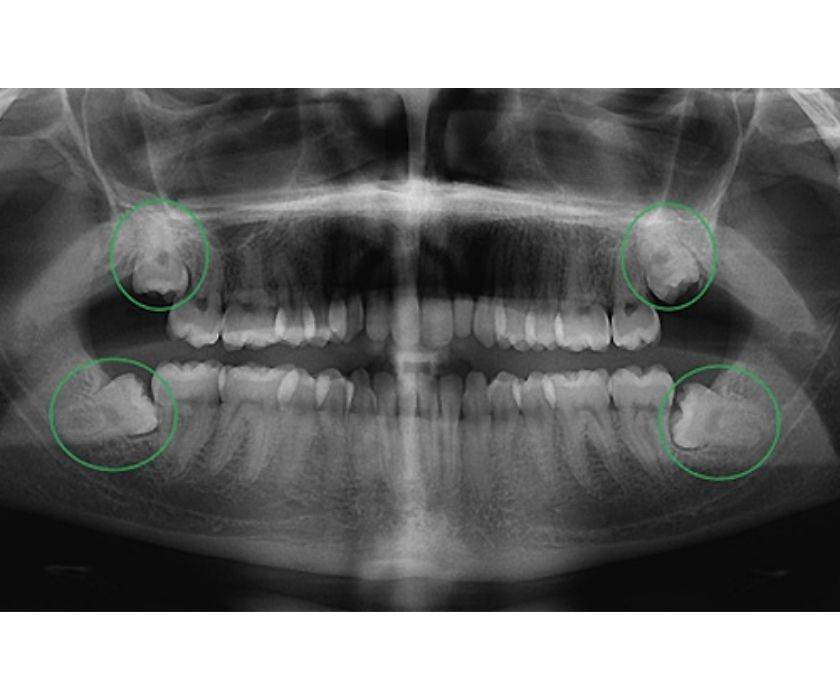

Hình chụp X-Quang răng khôn mọc lệch

Một ca nhổ răng khôn an toàn bắt đầu từ việc hiểu rõ về vị trí, hình dáng và tương quan của nó với các cấu trúc giải phẫu quan trọng. Không thể chỉ dựa vào mắt thường hay phim X-quang 2D thông thường, vì chúng không cung cấp đủ thông tin chi tiết.

• Xác định chính xác vị trí và hướng mọc: Phim 3D cho thấy rõ ràng răng khôn đang mọc thẳng, mọc nghiêng hay mọc ngầm hoàn toàn.